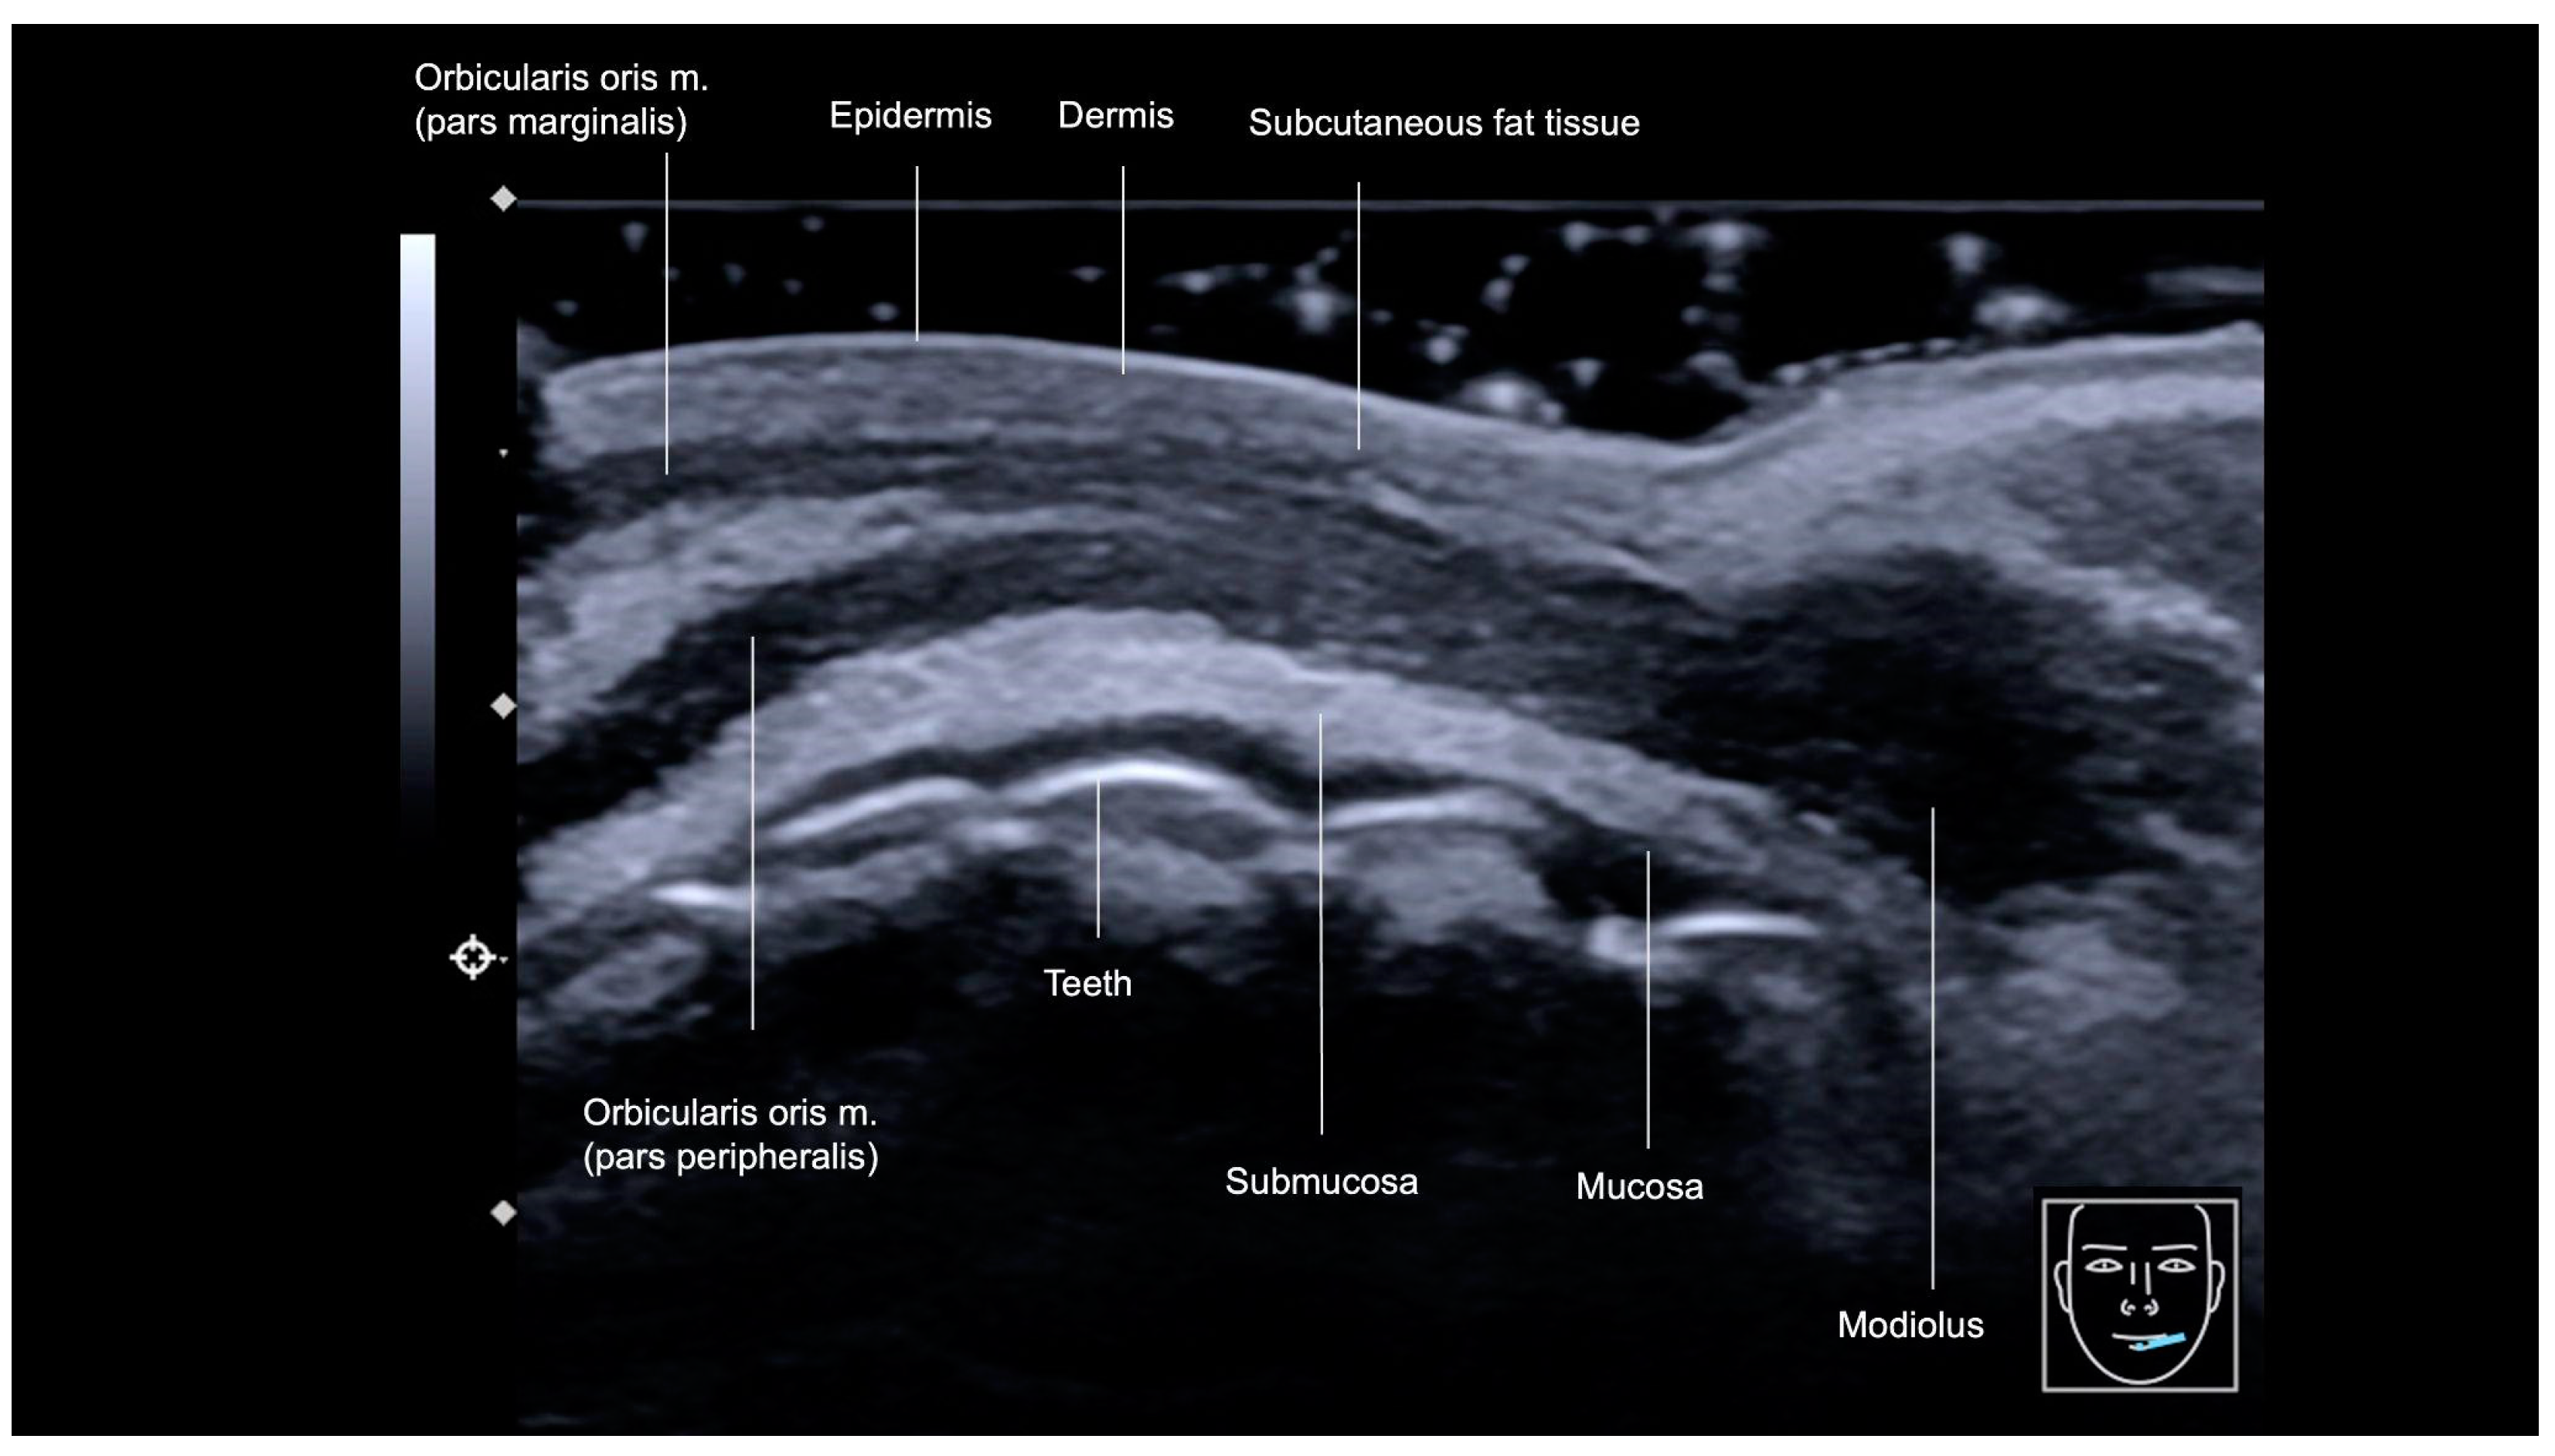

3.3.1. Sonographic Anatomy

3.3.2. Ultrasound-Guided Filling Techniques of the Lips